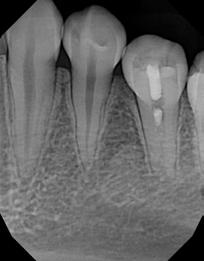

Employing revascularization by infiltrating stem cells from apical papilla and using them to treat immature necrotic tooth with periapical infection promotes root development and reduces fracture risk. Case report.